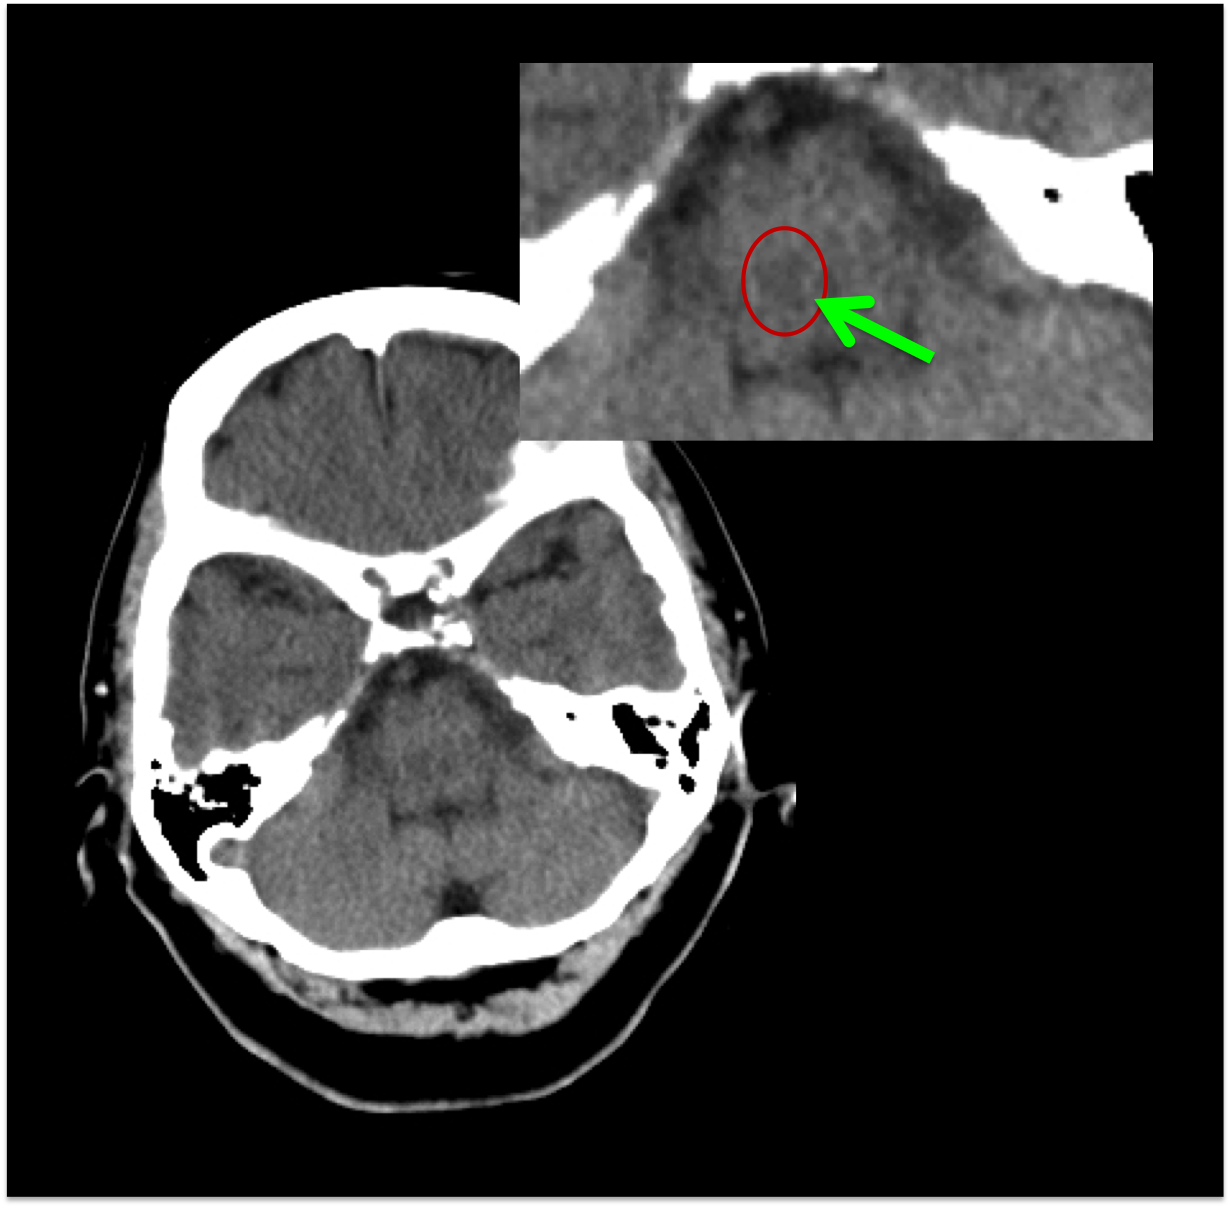

FRACTURAS DE CRÁNEO.

Con ventana de hueso.

Las reconstrucciones 3D-VR aumentan la capacidad diagnóstica de las fracturas desplazadas y no desplazadas.

La presencia de fractura no se correlaciona con la severidad del daño cerebral, sin embargo, la incidencia de hemorragia intracraneal es mayor en pacientes con fractura que en los que no la presentan. Al mismo tiempo, el 25% aprox. de pacientes con daños cerebrales fatales no muestran fractura de cráneo.

- Fracturas lineales = las más frec. -> baja incidencia de daño cerebral.

- Fracturas con hundimiento -> asocia contusiones y roturas durales.

- Fracturas de la base -> pueden ser transversas o diagonales, éstas con mayor índice de mortalidad. Pueden causar ceguera, afectación de pares craneales, pédida de audición, fuja de LCR. En las fracturas que afectan al canal carotídeo en su porción petrosa, merece la pena realizar un angioTC.